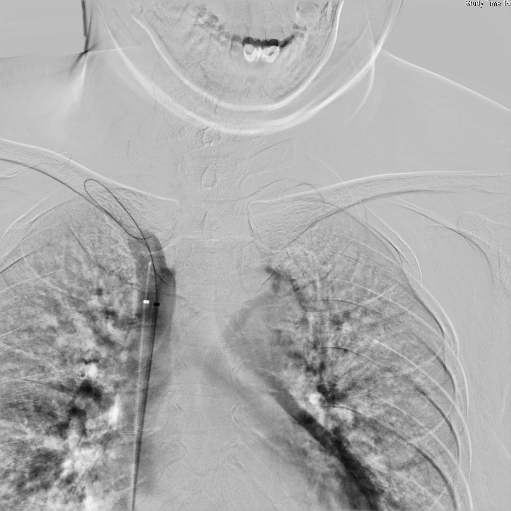

诊断:1、左头臂静脉闭塞,2、慢性肾衰竭尿毒症期,3、高血压。